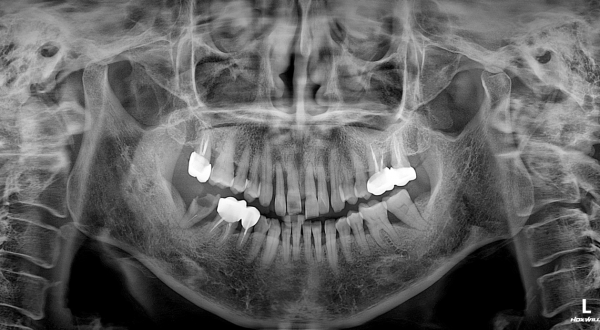

영상 및 구강 검사 소견

파노라마 및 CBCT 분석 결과,

* 전반적인 만성 치주염 소견

* 상·하악 치조골의 광범위한 흡수

* 특히 상악 전치부에서 수직·수평적 골 소실이 현저

* 치근 대비 잔존골 높이 및 폭 모두 제한적

즉, 환자가 느끼는 불편은 앞니였으나

실제 문제는 이미 치조골 단계에서 진행 중인 상태였다.